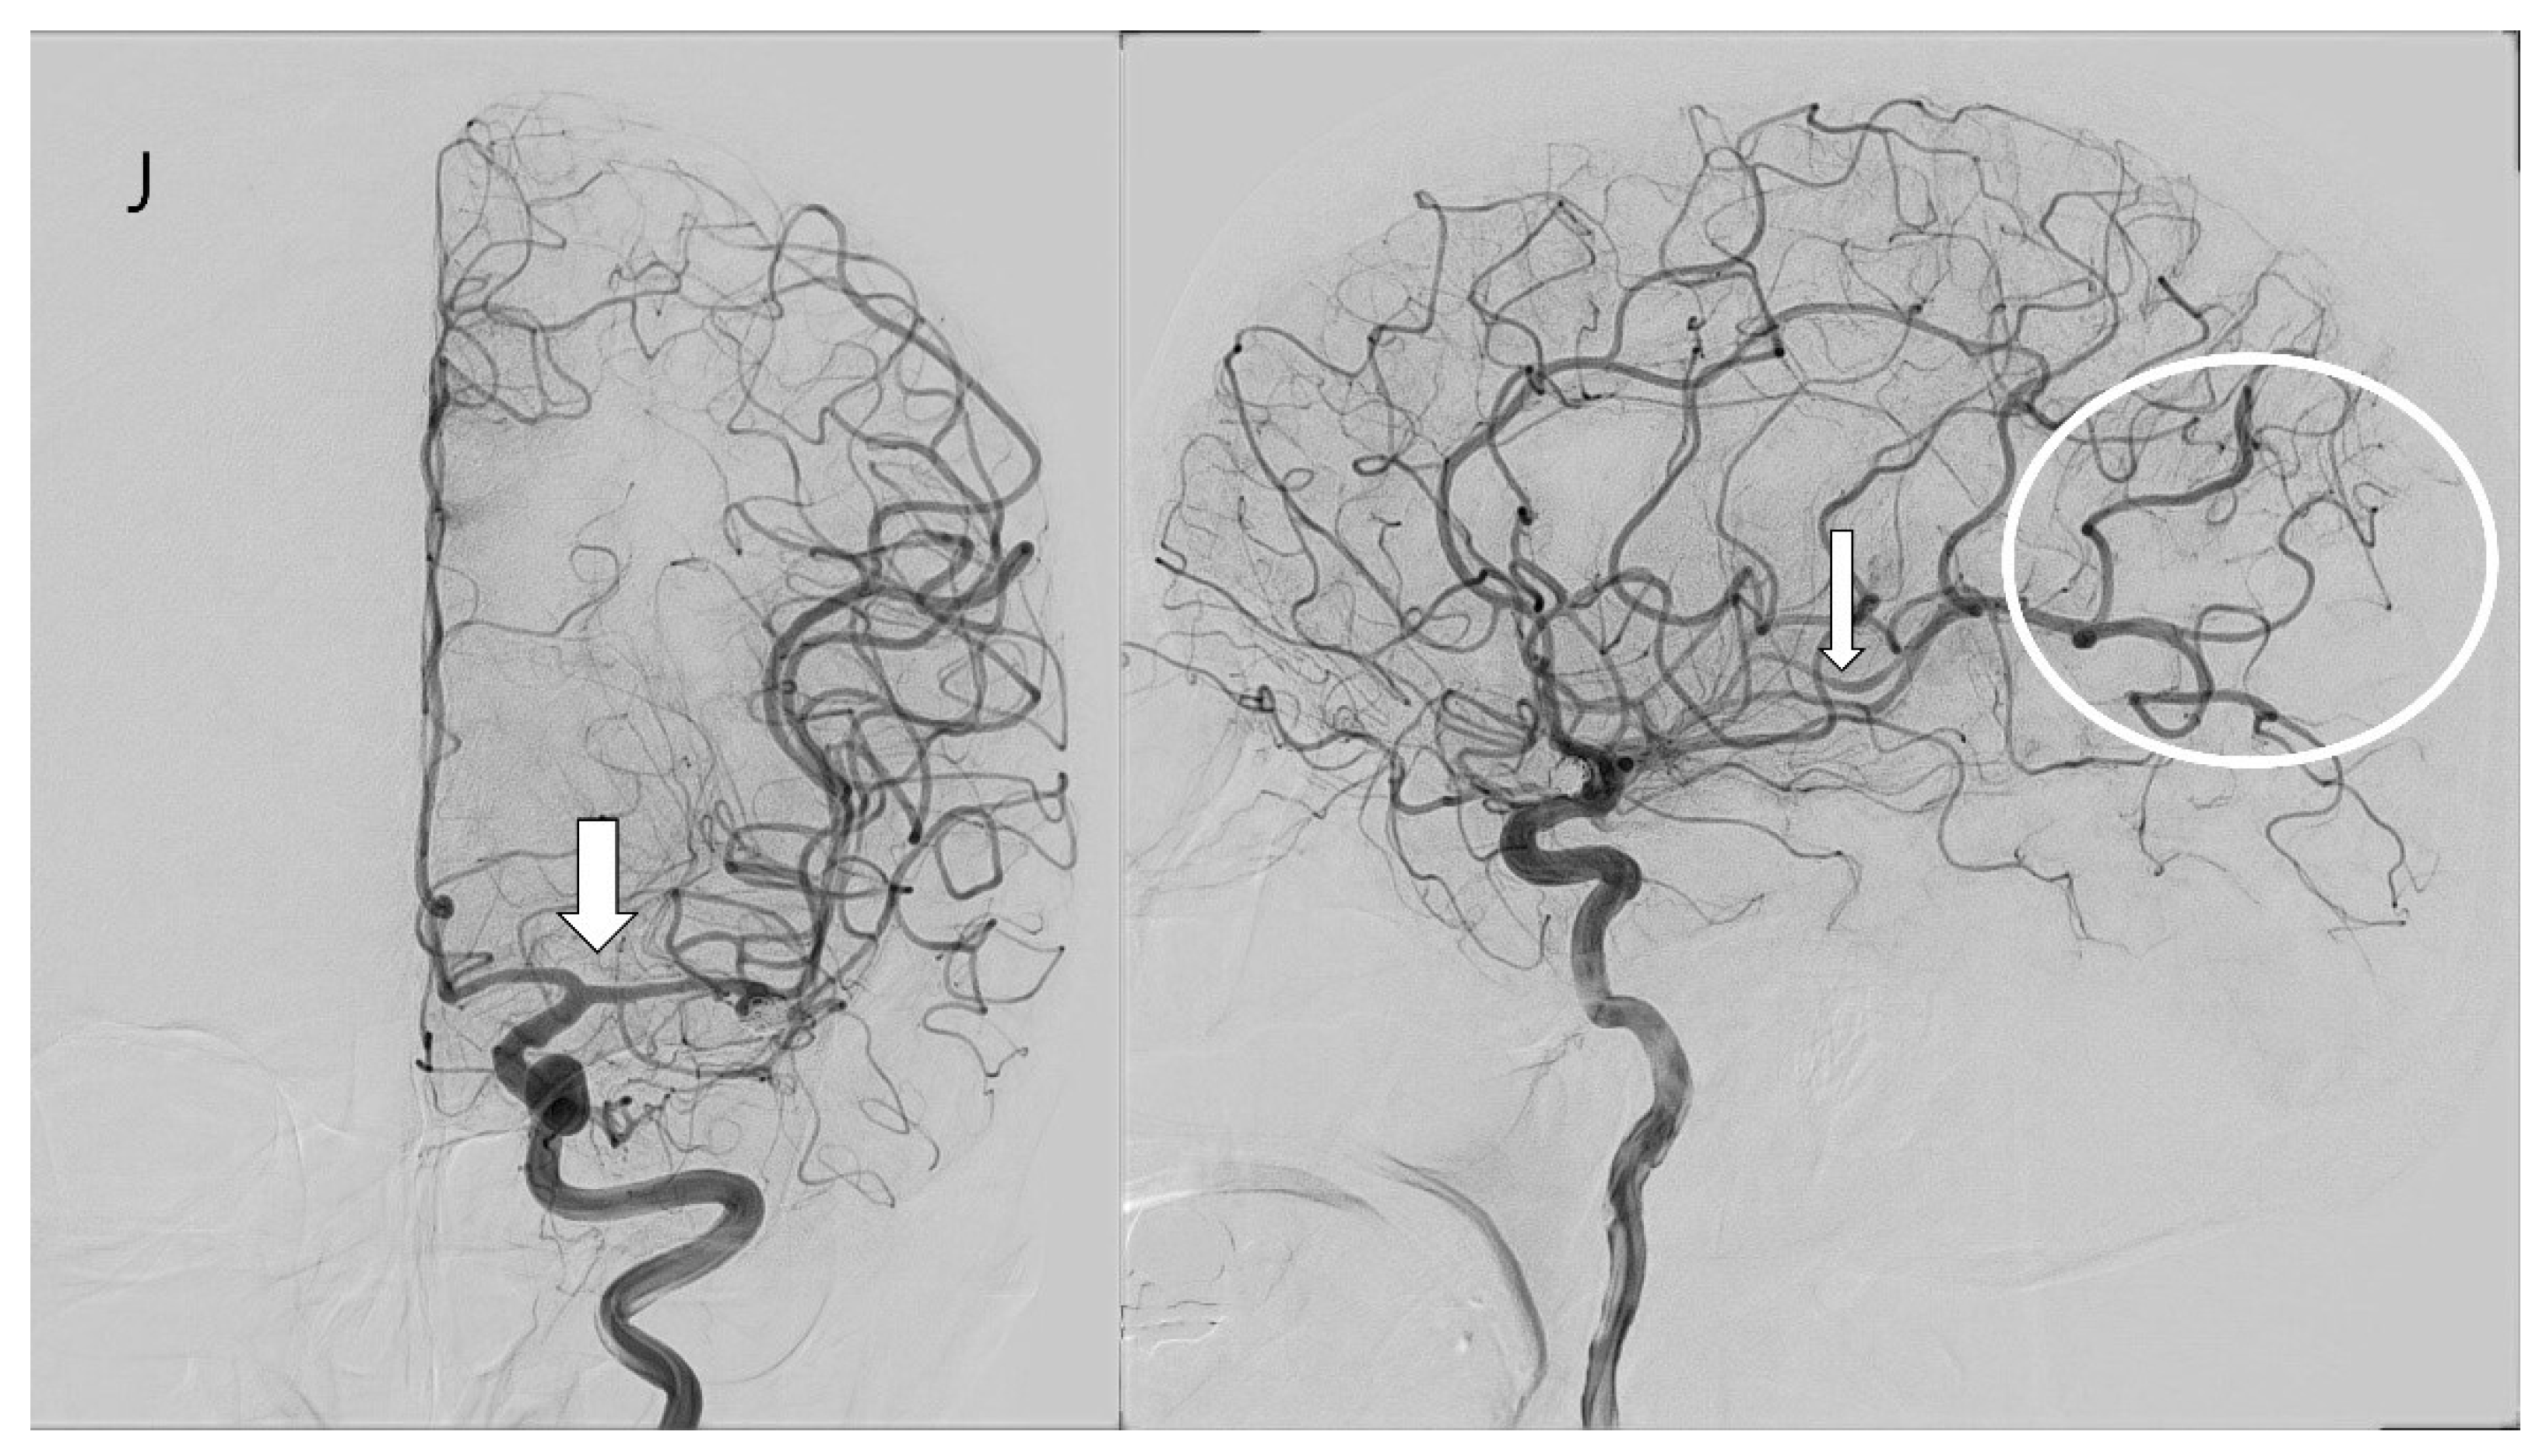

A fifty-year-old female patient with a severe headache visited our emergency room. She had hypertension and had been taking a calcium channel blocker. Initial brain CT and CT angiography revealed an aneurysmal subarachnoid hemorrhage (Hunt–Hess grade 2 and modified Fisher grade 3) due to a ruptured left MCA bifurcation aneurysm (Figure 3A). An emergent TFCA was performed, revealing the aneurysm to have a maximal size of 6.21 mm and a neck size of 3.21 mm. Emergent coil embolization using the double microcatheter technique was successfully performed. The ruptured aneurysm occluded completely without procedural complications (Figure 3B). We inserted a lumbar drain to treat mild hydrocephalus, and the patient was admitted to the ICU for intracranial pressure control and vasospasm prevention. Initial TCD ultrasonography was conducted the day after coil embolization (Figure 3C,D). TCD ultrasonography monitoring continued for 2 weeks to detect vasospasm. The blood flow velocity of the left MCA was increased slowly. However, the patient experienced no clinical symptoms except for a headache. Seven days after coil embolization, she complained of severe headache and left-side visual disturbance. Immediate follow-up TCD ultrasonography revealed severe vasospasm, the mean blood flow velocity having doubled (Figure 3E,F). TFCA was conducted to confirm and treat the vasospasm. TFCA revealed severe vasospasm in the cerebral vessels of the left hemisphere (Figure 3G: the white arrow and circle denote regions of decreased blood flow attributable to vasospasm). Intra-arterial nimodipine angioplasty was performed for 4 days, after which the vasospasm and her symptoms gradually improved (Figure 3H–J: the white arrow and circle highlight areas of restored blood flow following intra-arterial nimodipine angioplasty). She was discharged at 3 weeks after coil embolization without neurologic symptoms. Her mRS score at 6 months post-embolization was 0.

Figure 3.

Case illustration of patient who suffered subarachnoid hemorrhage.